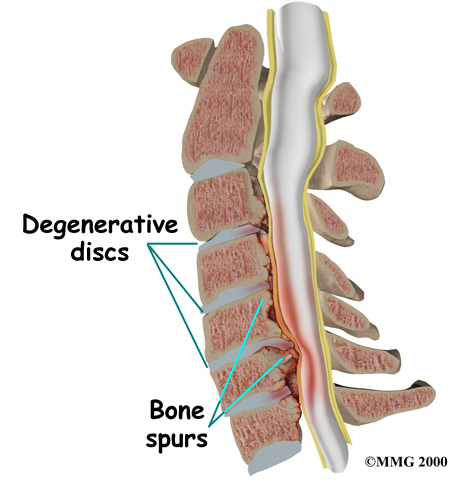

Degeneration is the most common cause of spinal stenosis. Wear and tear on the spine from aging and from repeated stress and strain can cause many problems in the cervical spine. The intervertebral disc can begin to collapse, shrinking the space between vertebrae. Bone spurs may form that protrude into the spinal canal and reduce the space available to the spinal cord. The ligaments that hold the vertebrae together may become thicker and can also push into the spinal canal. All of these conditions narrow the spinal canal.

Degeneration is the most common cause of spinal stenosis. Wear and tear on the spine from aging and from repeated stress and strain can cause many problems in the cervical spine. The intervertebral disc can begin to collapse, shrinking the space between vertebrae. Bone spurs may form that protrude into the spinal canal and reduce the space available to the spinal cord. The ligaments that hold the vertebrae together may become thicker and can also push into the spinal canal. All of these conditions narrow the spinal canal.

Some people are born with a spinal canal that is narrower than normal. This is called congenital stenosis. They may not feel problems early in life, but having a narrow canal to begin with places them at risk for stenosis. Even a minor neck injury can set them up to have pressure against the spinal cord. People born with a narrow spinal canal often have problems later in life, because the canal tends to become narrower due to the affects of aging. These degenerative changes often involve the formation of bone spurs (small bony projections) that point into the spinal canal and put pressure on the spinal cord.